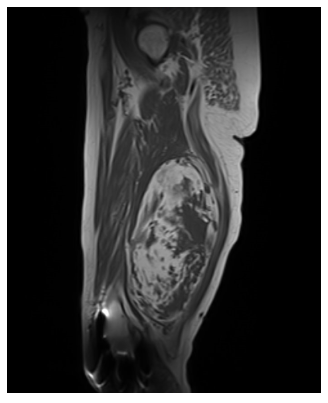

Radiographic imaging is used to help form a diagnosis. These include X-Ray, MRI, CT and Bone Scans

An example of an MRI is shown.